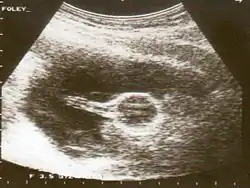

Catéter de Foley

Las sondas de Foley son tubos flexibles, generalmente de látex, que en la cateterización urinaria se pasan a través de la uretra y hacia el interior de la vejiga. Este procedimiento se realiza por varios objetivos, uno de ellos es para obtener una muestra de orina libre de gérmenes, o bien para ayudar a aliviar una vejiga distendida.[1] Quedan retenidos por medio de un globo en la extremidad del catéter que se infla con agua estéril.[2] Los globos vienen típicamente en dos tamaños diferentes, 5 cm³ y 30 cm³.[3]